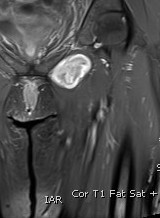

MRI

Target sign

- hypointense centrally

- hyperintense peripherally

Neurofibroma femoral nerve

Plexiform neurofibromas Neurofibromatosis Type 1

Multiple neurofibromas Neurofibromatosis Type 1